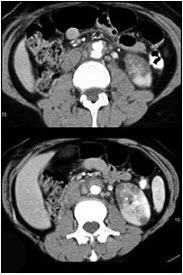

女,29岁,尿频、尿痛伴寒战高热3天。尿检:白细胞(+++),请结合图片作出最佳诊断 ( )

• A、左侧肾癌

• B、左侧急性肾盂肾炎

• C、左侧肾脓肿

• D、左侧肾结核

• E、左侧肾囊肿合并感染